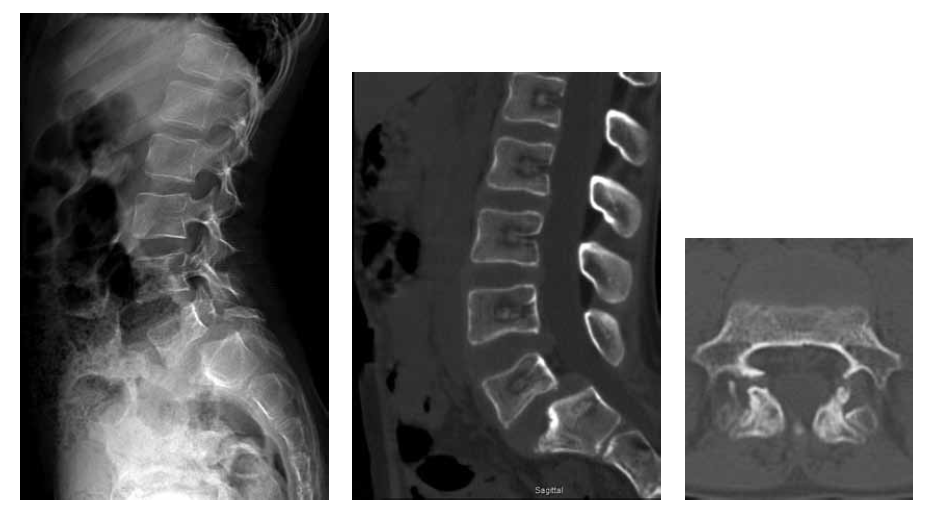

Considering the persistent pain syndrome after the conservative treatment and progressive nature of spondylolisthesis of L5, the following surgical intervention was performed: L5 laminectomy, microsurgical decompression of the spinal cord roots, complete reduction of the L5 vertebra, transpedicular fixation of the L5–S1 with additional fixation in the pelvic bone, and posterior interbody fusion of L5–S1. The duration of the surgery was 355 mins; the volume of blood lost was 800 ml. The patient was activated on the day 2 after surgery. During the postoperative period, the radicular pain syndrome had regressed completely, and no neurological disorders were detected. According to the control radiography, the restoration of the anatomical relationship of the vertebrae was noted. The position of the screws and implants was correct (Fig. 2). During the follow-up period, the patient had no complaints. After 1.5 years, MSCT revealed the formation of a reliable artifactual block, and the integrity of the surgical hardware was preserved (Fig. 3).

Fig. 3. MSCT of the lumbar spine 1.5 years after the surgery